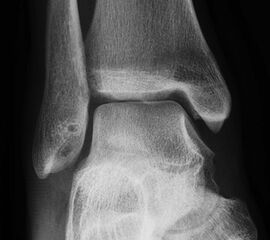

- Röntgenaufnahme des OSG in 2 Ebenen (seitlich und Mortiseview).

- MRT des OSG zur Beurteilung des ligamentären Schadens und möglicher Knorpelläsionen.

- Ggf. CT zur Bestimmung der Lage und Größe begleitender Osteophyten oder freier Gelenkkörper, sofern diese als Begleitpathologien vorliegen.

- Klinische Untersuchung und Dokumentation des Talusvorschubs, des lateralen und des medialen Tilts sowie der Rotationsinstabilität.